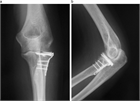

1. 橈骨頭骨折、橈骨頸部骨折の解剖学的特徴を把握する。

1. 橈骨頭骨折、橈骨頸部骨折は上腕骨小頭と橈骨頭が衝突して生じる。

1. 成人では橈骨頭に加え橈骨頚部も骨折しやすいが、小児では多くが橈骨頚部骨折である。